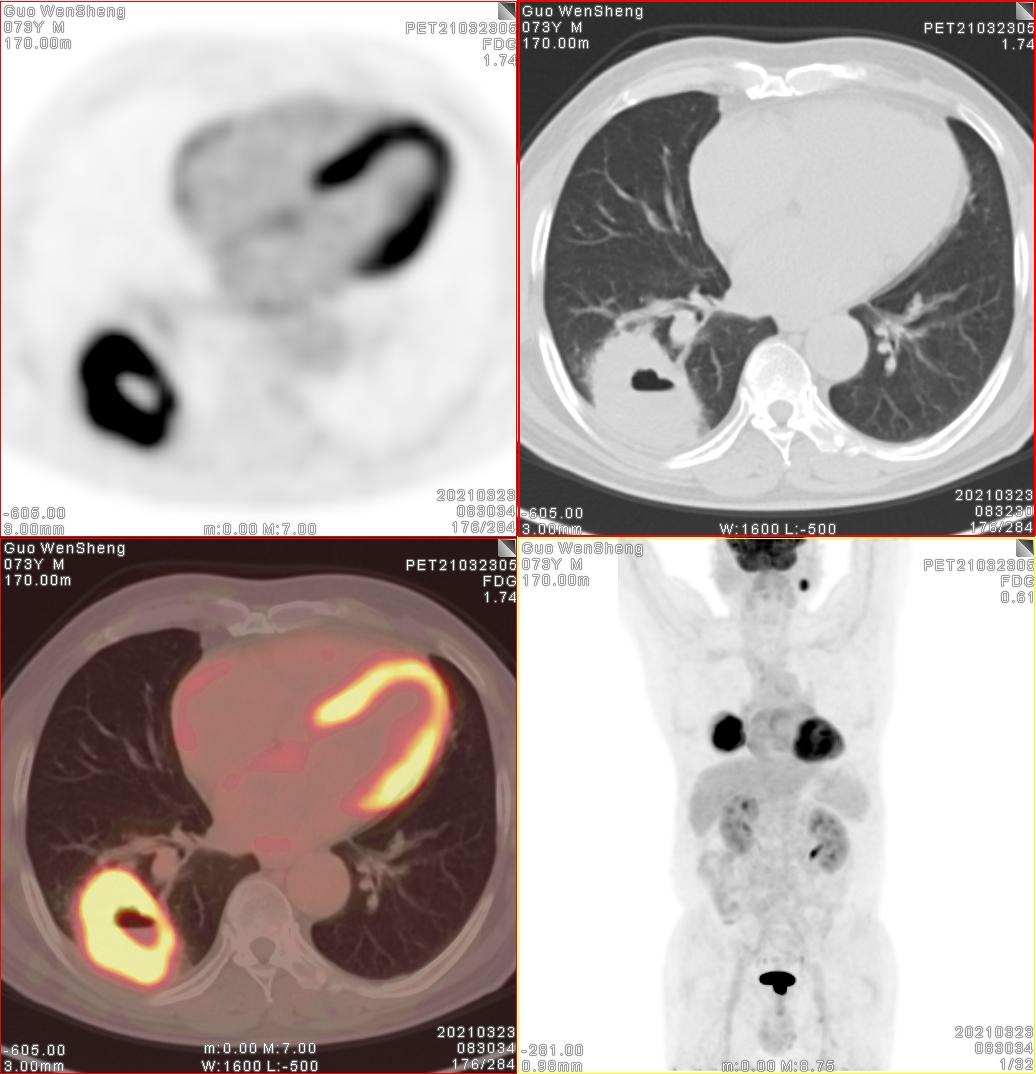

就在下班即将离开的时候,1个月以前的患者家属打来电话咨询下一步复查的事情。73岁的一位老者,经常还跑步锻炼,就是突发的咳嗽痰中带有黑色的痰液。1个月前做完检查,右肺下叶一个7.5cm以上的大肿块,我们考虑为肺癌以后马上做了胸腔镜手术。病理结果也非常的好,切除下来的淋巴结、胸膜都未发现转移。巫医生也是非常的欣慰,向这么大的病灶没有转移,也是非常的幸运。患者1个月恢复的很好。

最大径7.5cm,病理:腺癌

如此大的病灶没有发生转移

听到这位家属主动打来的电话,心情好多了。这个病灶切除了右肺下叶,虽然3A期,但是完整切除,引流区淋巴结也没有转移。3期的病灶切除这么完整非常幸运。最终病理是鳞癌,也做了基因检测,没有合适的靶向药。但根据身体状态,如果辅助以化疗,最终效果应该会不错。